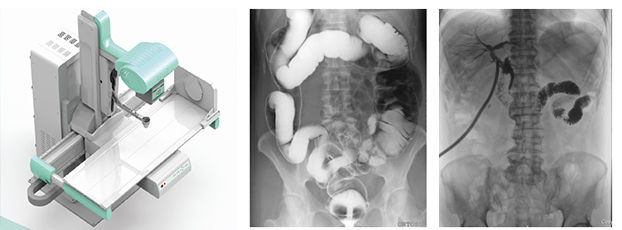

動(dòng)態(tài)DR是一種醫(yī)用X射線診斷設(shè)備的名稱,相比于普通DR的單一功能,動(dòng)態(tài)DR集合拍片、造影、胃腸、透視等多種功能,大幅提高診斷效率,避免漏診、誤診。擁有一臺(tái)動(dòng)態(tài)DR相當(dāng)于擁有整個(gè)放射科,能夠滿足普放科的常規(guī)拍片、胃腸造影、透視檢查等基本篩查功能需求。

動(dòng)態(tài)DR可以進(jìn)行實(shí)時(shí)造影劑追蹤、食道骨骼復(fù)位、輸卵管造影,實(shí)現(xiàn)全自動(dòng)攝影,通過透視消除常規(guī)DR的盲拍實(shí)現(xiàn)直接快速定位和精細(xì)診斷;具有豐富的數(shù)字化圖像處理軟件,性能良好,圖像分辨率高,能為醫(yī)生的臨床診斷提供了更優(yōu)異的影像數(shù)據(jù),提高診斷效率,大幅提高醫(yī)院工作效率。

普利德動(dòng)態(tài)DR臨床用途廣泛,一臺(tái)機(jī)器多種用途,可應(yīng)用于臨床各科室,如體檢科、內(nèi)科、外科、骨科、創(chuàng)傷科、急診科等。當(dāng)作為一臺(tái)普通DR X光機(jī)使用時(shí),能解決適用于全身各部位的數(shù)字化攝影,包括常規(guī)攝影(立位攝影、臥位攝影等,如胸片、頸椎、腰椎、腹部、頭顱、四肢等)和特殊攝影(傾斜攝影、角度攝影等,如瓦氏位、骶髂關(guān)節(jié)、髕骨軸位、跟骨軸位等);當(dāng)作為具有透視功能的胃腸機(jī)使用時(shí),能解決適用于全身各部位的數(shù)字化透視(如胸透、腹透等)、透視下定位、透視下穿刺及透視下數(shù)字點(diǎn)片攝影,還能解決適用于胃腸道造影檢查,如食管造影、上消化道造影、全消化道造影等,以及數(shù)字化造影檢查,如如口服膽囊造影、靜脈膽道造影、T管造影、逆行胰膽管造影(ERCP)、靜脈腎盂造影(IVP)、子宮輸卵管造影、脊髓造影等。

普利德動(dòng)態(tài)DR具備動(dòng)態(tài)影像視頻實(shí)時(shí)回放功能,探測器采集大幅面,進(jìn)行透視、胃腸、造影檢查更加方便、準(zhǔn)確,明顯提高檢查效率及診斷質(zhì)量。操作簡單快捷,一鍵到位。充分體現(xiàn)人性化設(shè)計(jì)理念,可根據(jù)檢查部位的不同調(diào)整采像速度,實(shí)時(shí)采集高品質(zhì)影像;高端人性化設(shè)計(jì)的檢查床,無需移動(dòng)病人即可完成各項(xiàng)檢查。具有自動(dòng)亮度跟蹤功能,在方便操作的同時(shí),通過自動(dòng)優(yōu)化曝光劑量獲得優(yōu)異的影像圖片,有效降低X射線輻射劑量,保護(hù)醫(yī)患身體健康。

擁有先進(jìn)的數(shù)字化圖像處理技術(shù),保證優(yōu)異的動(dòng)、靜態(tài)圖像質(zhì)量。動(dòng)態(tài)CCD探測器技術(shù),可進(jìn)行高像素動(dòng)、靜態(tài)圖像轉(zhuǎn)換,采集的圖像具有信息量大、對比度高和動(dòng)態(tài)范圍寬的特點(diǎn),成像質(zhì)量明顯優(yōu)于普通胃腸機(jī),為醫(yī)生的臨床診斷提供更優(yōu)異的影像數(shù)據(jù),大幅提高醫(yī)院的工作效率。